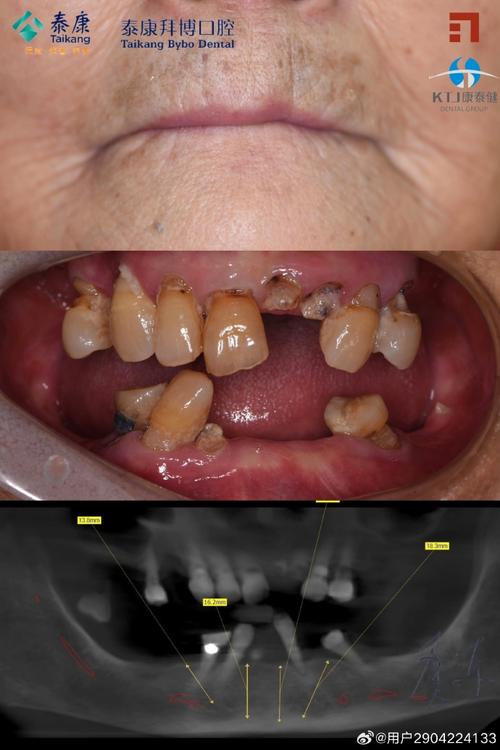

案例2:退休阿姨王阿姨,后牙剧痛无法进食(62岁,退休教师)

问题:后牙反复疼痛3天,吃药无效,牙龈肿起“脓包”,连稀饭都吃不下。

过程:

- 拜博医生检查发现:牙齿III度龋坏,牙根尖有脓肿,无法保留;

- 先进行“根管开放引流”,缓解疼痛,3天后炎症消退,拔除坏牙;

- 牙槽骨条件尚可,即刻种植植入种植体,安装临时牙冠;

- 2个月后更换永久全瓷牙,现在能正常吃坚果、啃排骨,生活质量大幅提升。